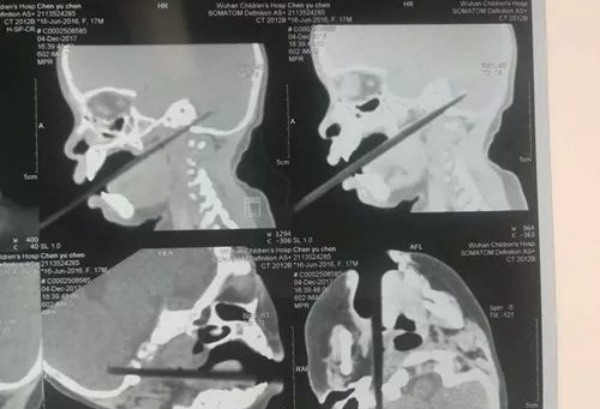

Người nhà vội vã đưa cháu bé đến bệnh viện, bác sĩ đã chụp CT và sắp xếp ca phẫu thuật sớm nhất.

Trong quá trình phẫu thuật, bác sĩ phát hiện ra rằng đũa được đưa vào tiểu não khoảng 2 cm, và tĩnh mạch cổ bên trong bị cọ xát. Điều tồi tệ nhất là chiếc đũa có hạt cơm dính trên đầu đã đâm vào tĩnh mạch cảnh trong. May mắn thay, ca mổ đã thành công.

Yang Yang ngay lập tức được đưa đến bệnh viện, tại đây, các bác sĩ phát hiện chiếc đũa đâm sâu vào não bé. Ca phẫu thuật được tiến hành với sự tham gia của một nhóm chuyên gia liên khoa. Các bác sĩ thần kinh mở hộp sọ cậu bé từ phía sau đầu, tiếp cận hố sau của sọ để tìm đầu đũa.

Cuộc phẫu thuật khó khăn nhất ở công đoạn gây mê. Vì theo các chuyên gia, họ không thể đeo mặt nạ dưỡng khí cho cậu bé vì có thể gây nguy hiểm vì chiếc đũa vẫn nhô ra khỏi miệng.

Do đó, họ phải cắt phần thò ra của chiếc đũa trước rồi mới úp được chiếc mặt nạ lên mặt Yang Yang.